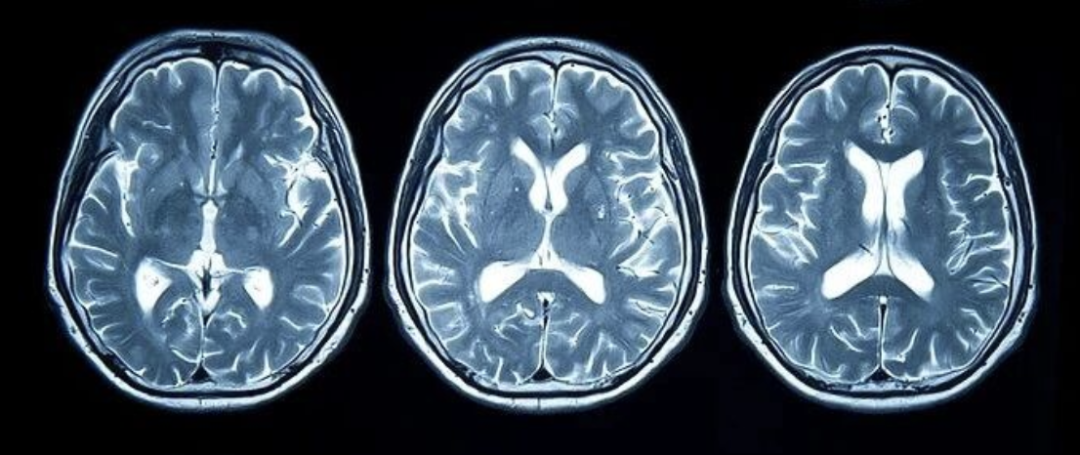

脑梗又称“缺血性脑卒中”,是由于脑血管阻塞,导致脑部血液循环障碍,缺血缺氧引起的局部脑组织缺血性坏死。发病时,患者可表现为语言障碍、肢体麻木、视物异常及头晕头痛等。